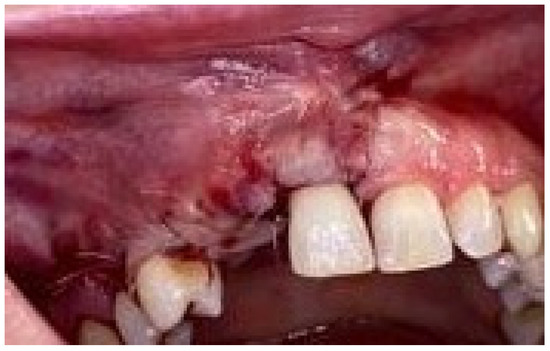

Surgical removal of impacted mandibular third molars constitutes one of the most frequently performed procedures within oral surgery. This surgery procedure is associated with many post-operative complications. Advanced platelet-rich fibrin (A-PRF) belongs to the second generation of platelet concentrates and is rich in numerous growth factors. The aim of this study was to assess the influence of A-PRF on selected clinical features following the surgical removal of impacted mandibular third molars. The research was conducted on 100 generally healthy patients, who underwent a lower third molar odontectomy in Department of Oral Surgery, Medical University of Gdańsk, Poland, between 2018 and 2019. The research group consisted of 50 patients (immediate A-PRF socket filling) and control group (50 patients without A-PRF socket filling). During the study, the following clinical features were assessed: pain (visual analog scale), analgesics intake, the presence of trismus, edema, hematomas within the surrounding tissues (e.g., cheek), prevalence of pyrexia, dry socket, secondary bleeding, presence of hematomas, skin warmth in the post-operative area, and bleeding time observed by the patient were analyzed on the 3rd, 7th, and 14th day after the procedure. There was a significant association between A-PRF socket filling and pain intensity, the analgesics intake, trismus, and edema on the 3rd and the 7th day (p < 0.05). The presence of hematomas and skin warmth on the 3rd day after the surgery (p < 0.05) were also statistically associated with A-PRF use. The study showed that in reducing the incidence of postoperative complications, A-PRF was more important than the position of the tooth or the duration of the procedure. The growth factors in A-PRF reduce postoperative complications, such as pain, trismus, edema, analgesics intake, presence of hematomas, and skin warmth, after mandibular wisdom teeth odontectomy. Full article